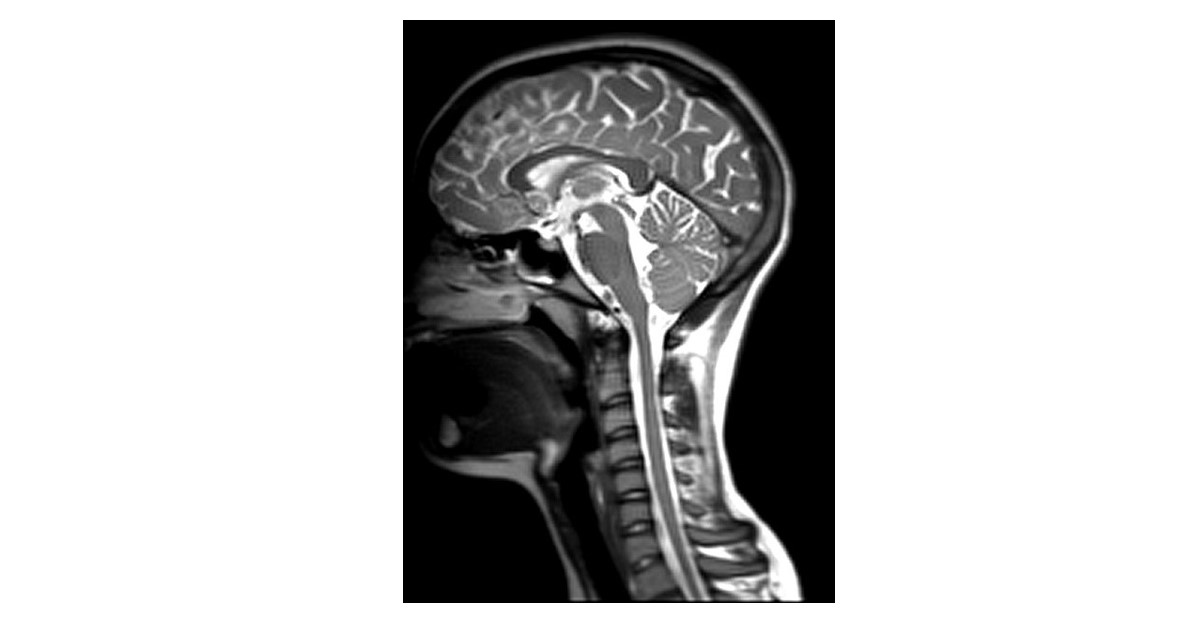

Chronic pain presents many challenges for research. Pain is highly individual and assessments of pain based on self-reports are subjective. In addition, pain is strongly influenced by emotional, cognitive, and health factors. Regions of the central nervous system that are involved with nociception and pain are inaccessible in human research participants except by means of neuroimaging. In recent years, neuroimaging methods have provided important new insights into the neuroanatomy and neurophysiology involved with nociceptive processing and pain perception in both healthy populations and in patients with chronic pain conditions. The studies to date span across the brain, brainstem, and spinal cord and have demonstrated effects such as placebo analgesia, the temporal summation of pain, and the modulation of pain in relation to mood, attention focus, listening to music, and cognitive tasks. Altered neural processes have also been identified in relation to altered pain sensitivity in chronic pain conditions and disease states. These results have provided new insights into individual differences in pain responses, factors that influence descending pain regulation, and how the state of pain sensitivity is modulated on a continual basis. The goal of this Research Topic is to compile novel and innovative neuroimaging studies, in humans or in animals, that further advance our understanding of altered neural processes related to chronic pain conditions.